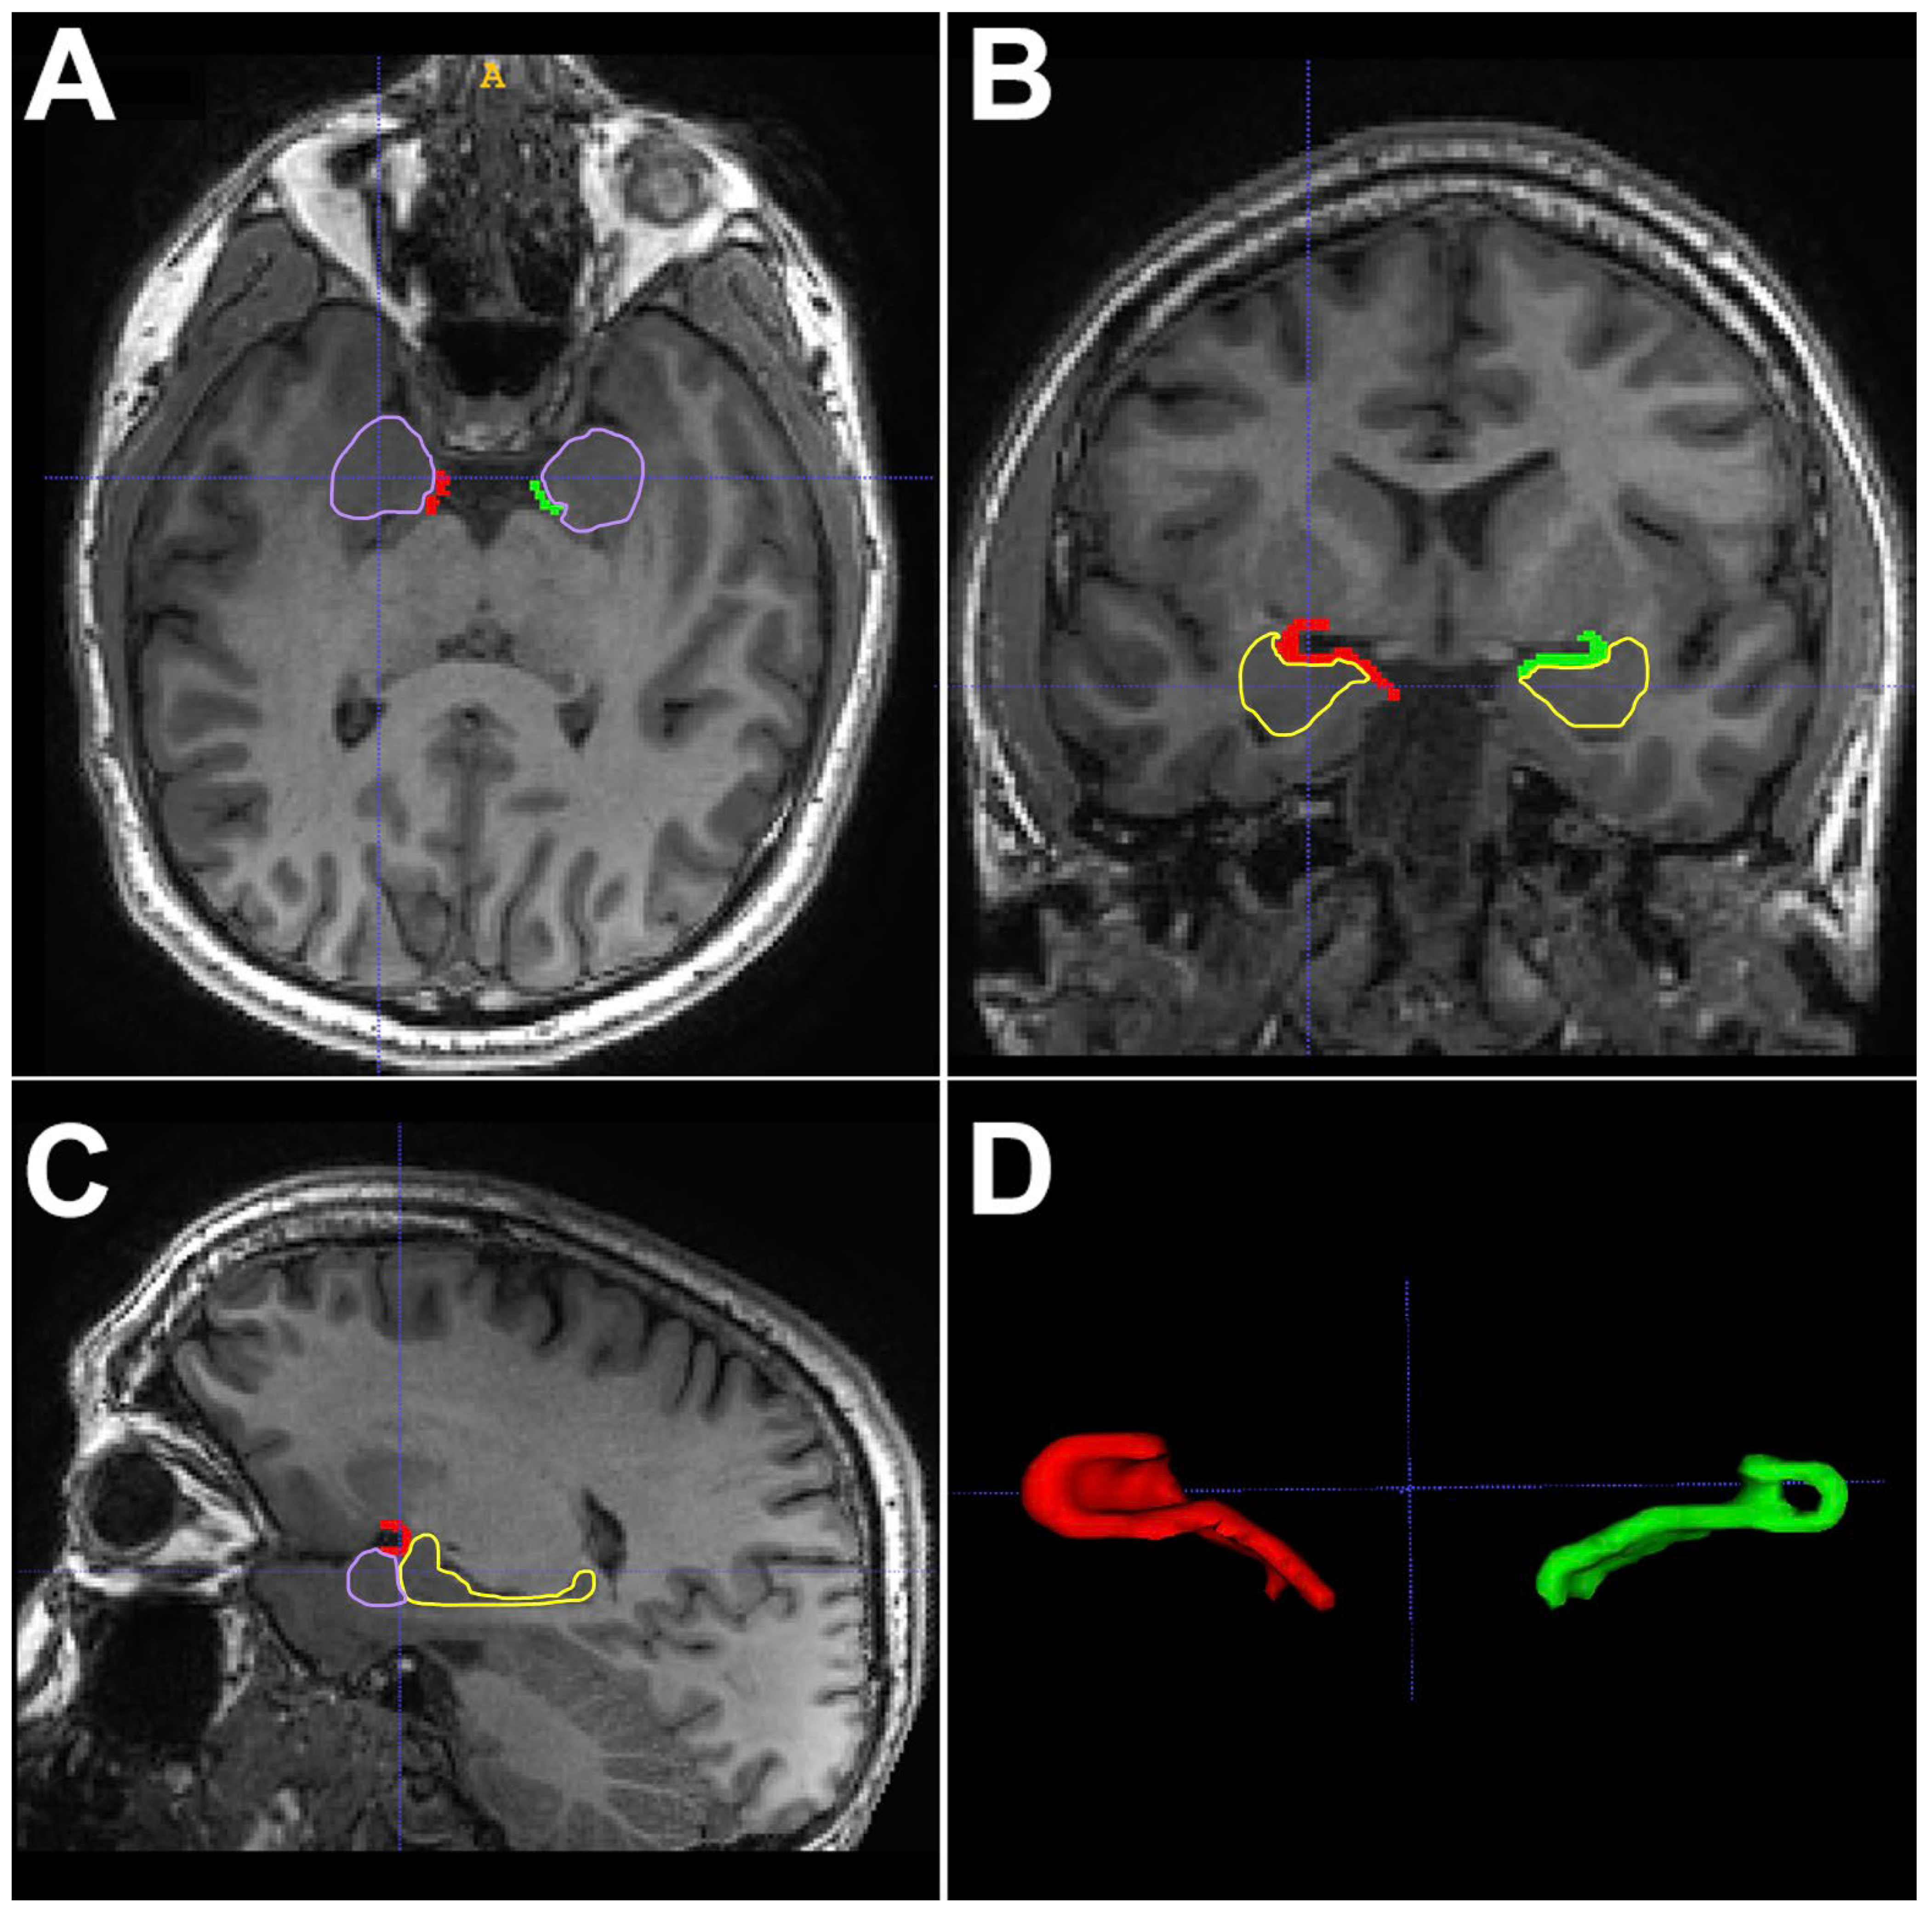

- Leon-Rojas, J.E.; Iqbal, S.; Vos, S.B.; Rodionov, R.; Miserocchi, A.; McEvoy, A.W.; Vakharia, V.N.; Mancini, L.; Galovic, M.; Sparks, R.E.; et al. Resection of the piriform cortex for temporal lobe epilepsy: A Novel approach on imaging segmentation and surgical application. Br. J. Neurosurg. 2021, 38, 716–721. [Google Scholar] [CrossRef]

- Iqbal, S.; Leon-Rojas, J.E.; Galovic, M.; Vos, S.B.; Hammers, A.; de Tisi, J.; Koepp, M.J.; Duncan, J.S. Volumetric analysis of the piriform cortex in temporal lobe epilepsy. Epilepsy Res. 2022, 185, 106971. Available online: https://linkinghub.elsevier.com/retrieve/pii/S092012112200122X (accessed on 20 September 2024).